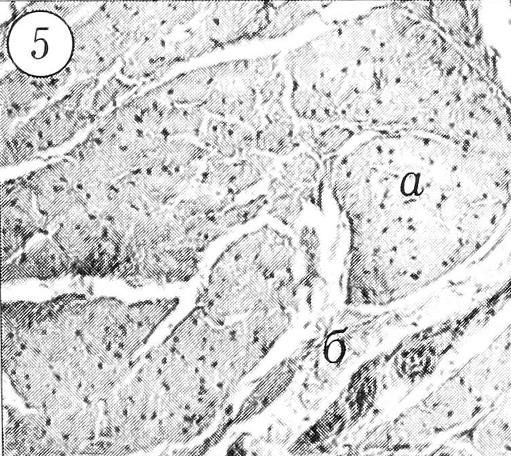

Рис. 3. Хрящ на границе с костью: а — зона энхондрального роста; б — новообразующаяся костная ткань. Ув. 11x9.

Рис. 4. Тяж смешанной структуры: а — гиалиновый хрящ; б — волокнистая соединительная ткань. Ув. 7,1x9.